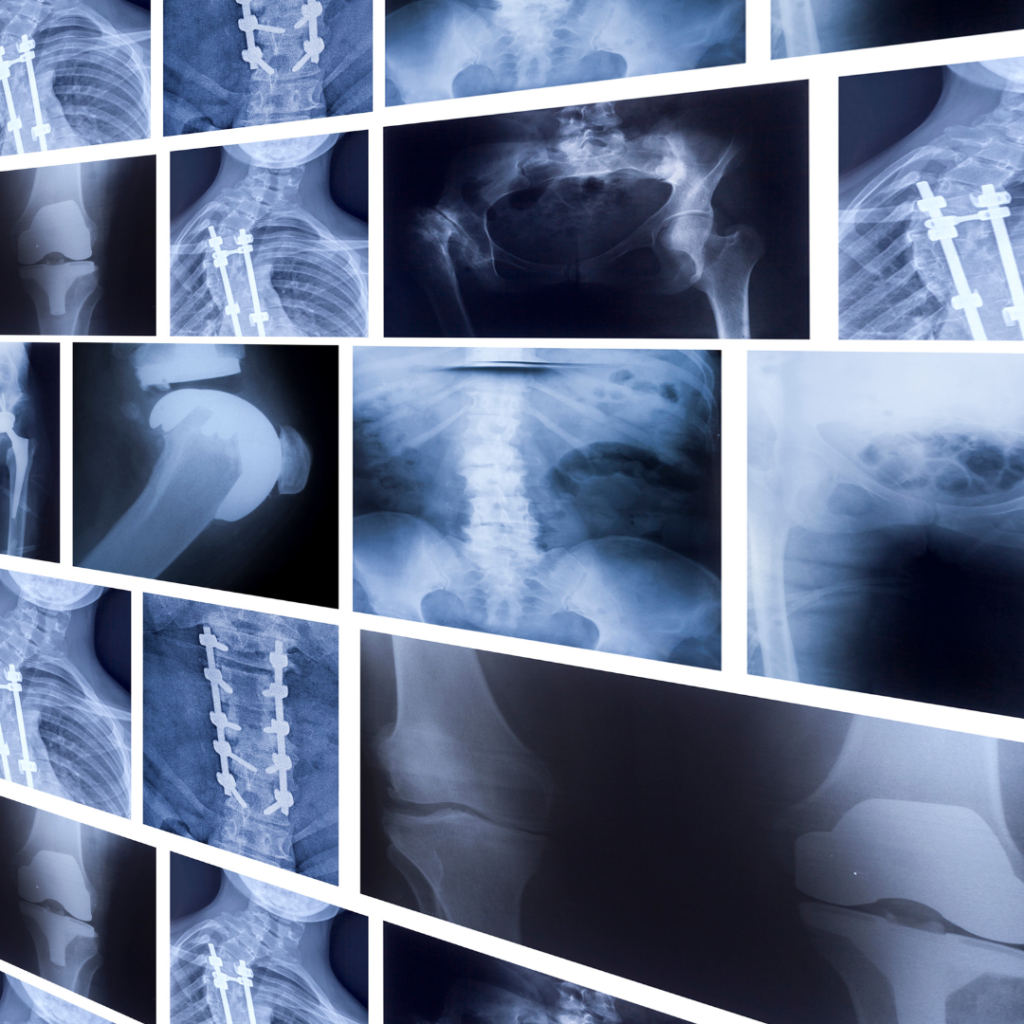

医療の現場では、レントゲンやMRIなどの画像検査が行われます。

その際、「年齢相応の変化があります」と説明されることは珍しくありません。

実は、こうした画像上の変化は、痛みを感じていない人にも多く見られることが分かっています。

つまり、体の中に変化が見つかったからといって、それが今感じている痛みの原因とは限らないのです。